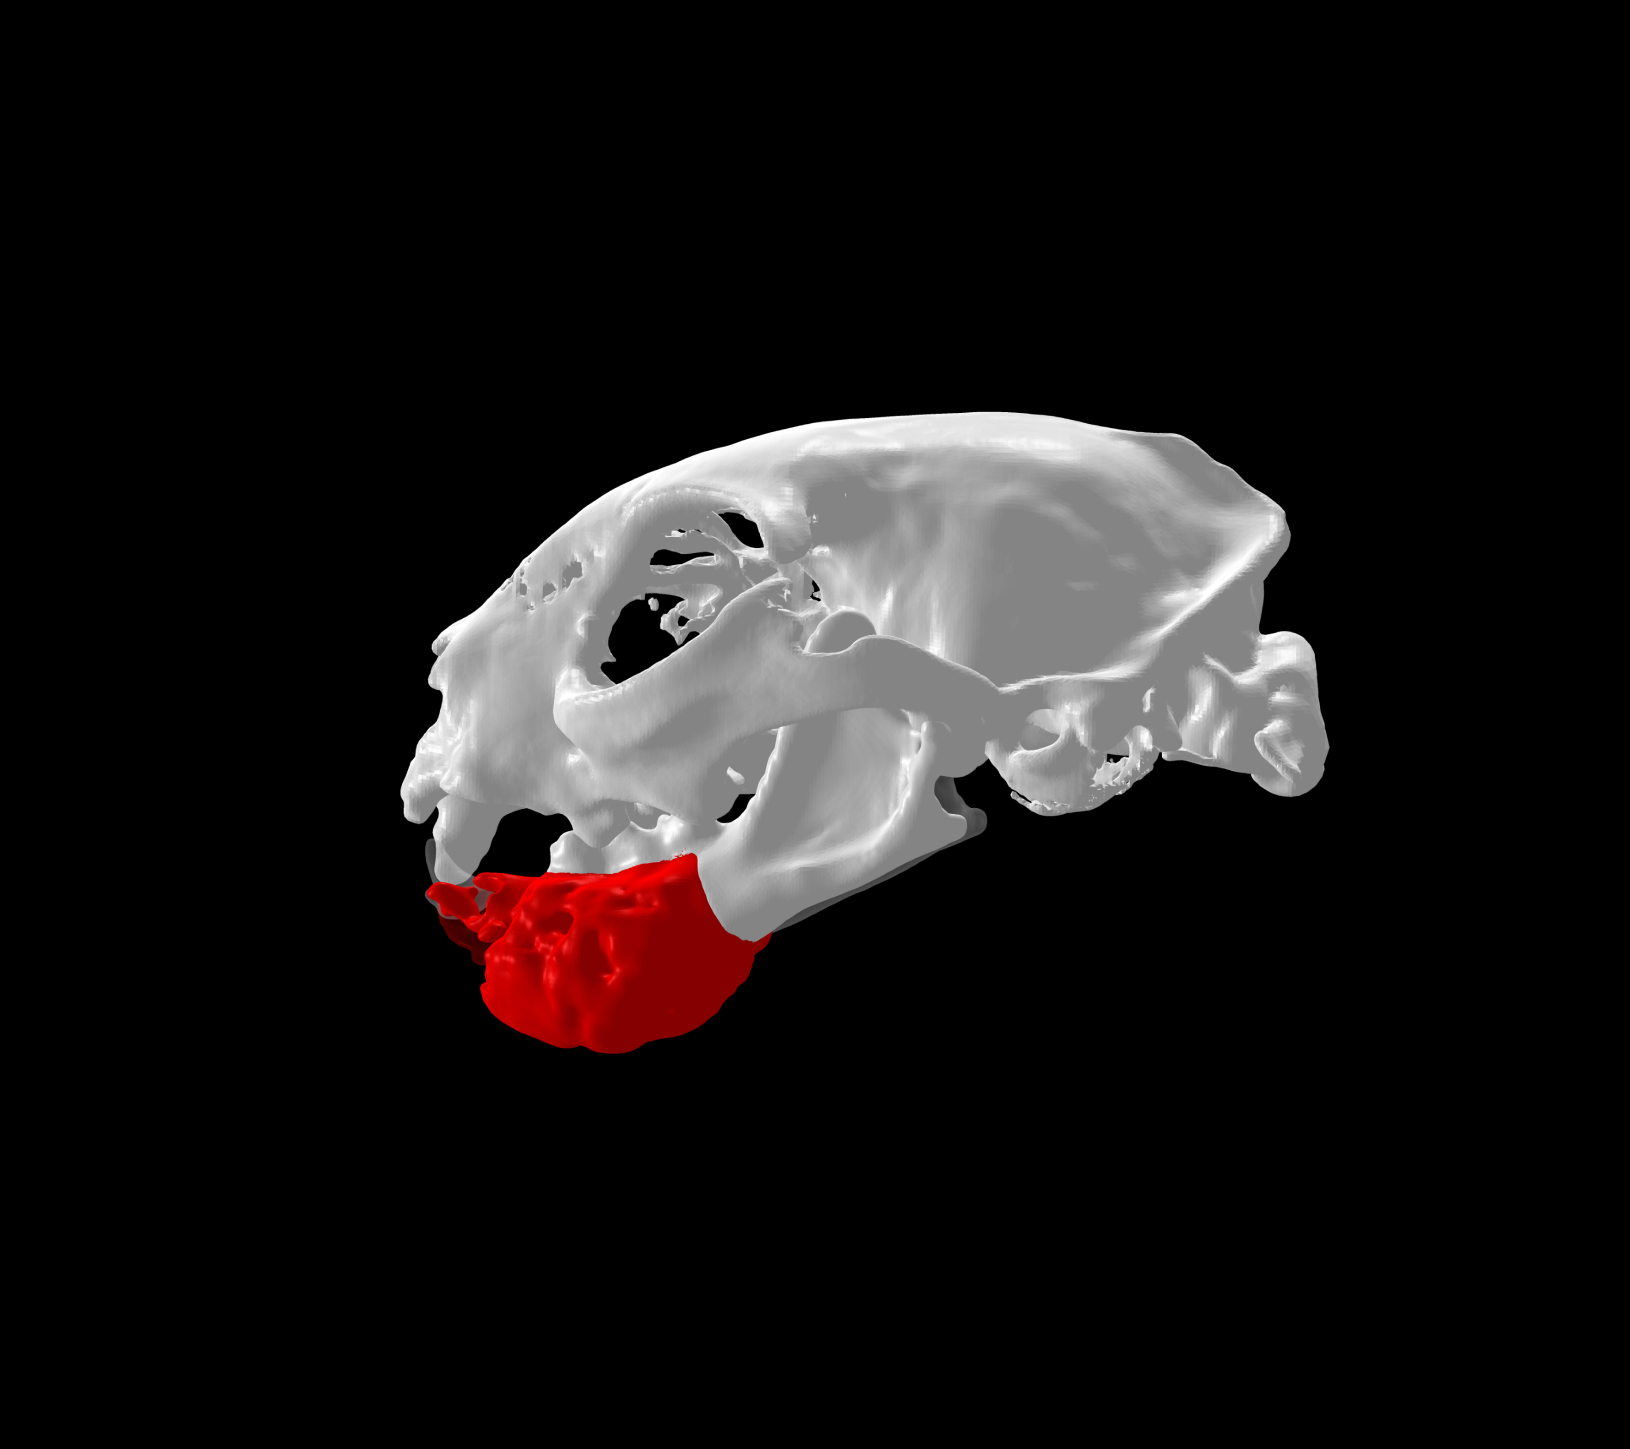

La customización de implantes quirúrgicos se refiere a la adaptación de los mismos a las necesidades de cada paciente, siendo personalizados a la anatomía única de cada individuo.

Esto se consigue gracias a los avances en la tecnología de fabricación, como la impresión 3D. Con esta tecnología se pueden crear implantes personalizados tanto en acero quirúrgico como en titanio a partir de imágenes médicas de tomografías computerizadas (TC) o resonancias magnéticas (RM).

- Mejor ajuste y adaptación al paciente: favorece la colocación precisa y la estabilidad del implante sobre la anatomía quirúrgica.